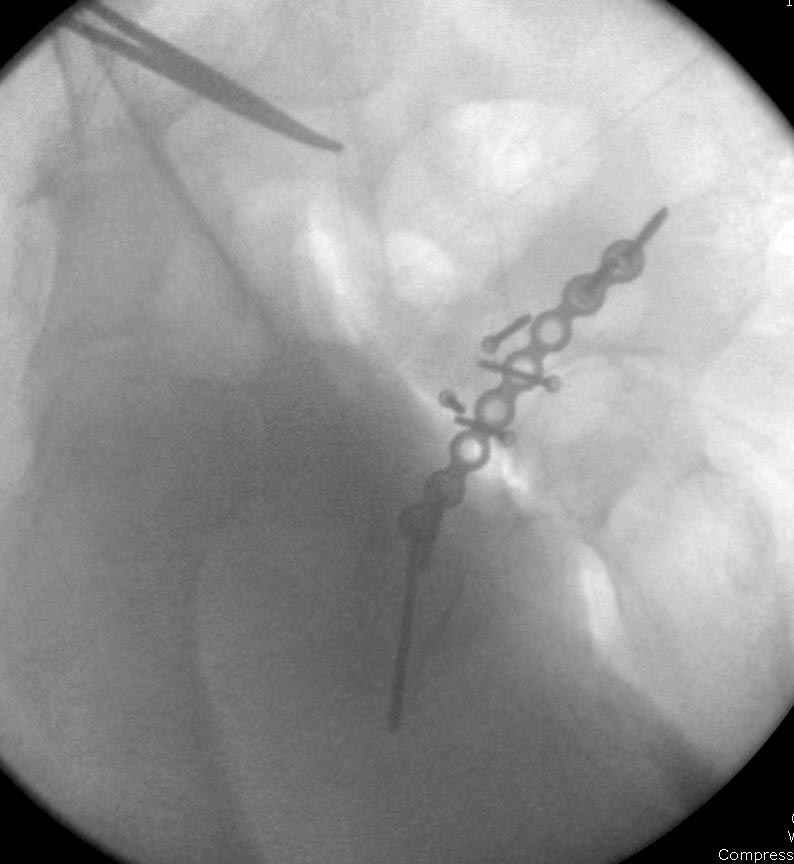

Интраоперционные N5 косая запирательная и N6 подвздошный снимок

11:50 больной в послеоперационной, рентгенограмма N7, компьютерная томограмма в тот же день N8-10